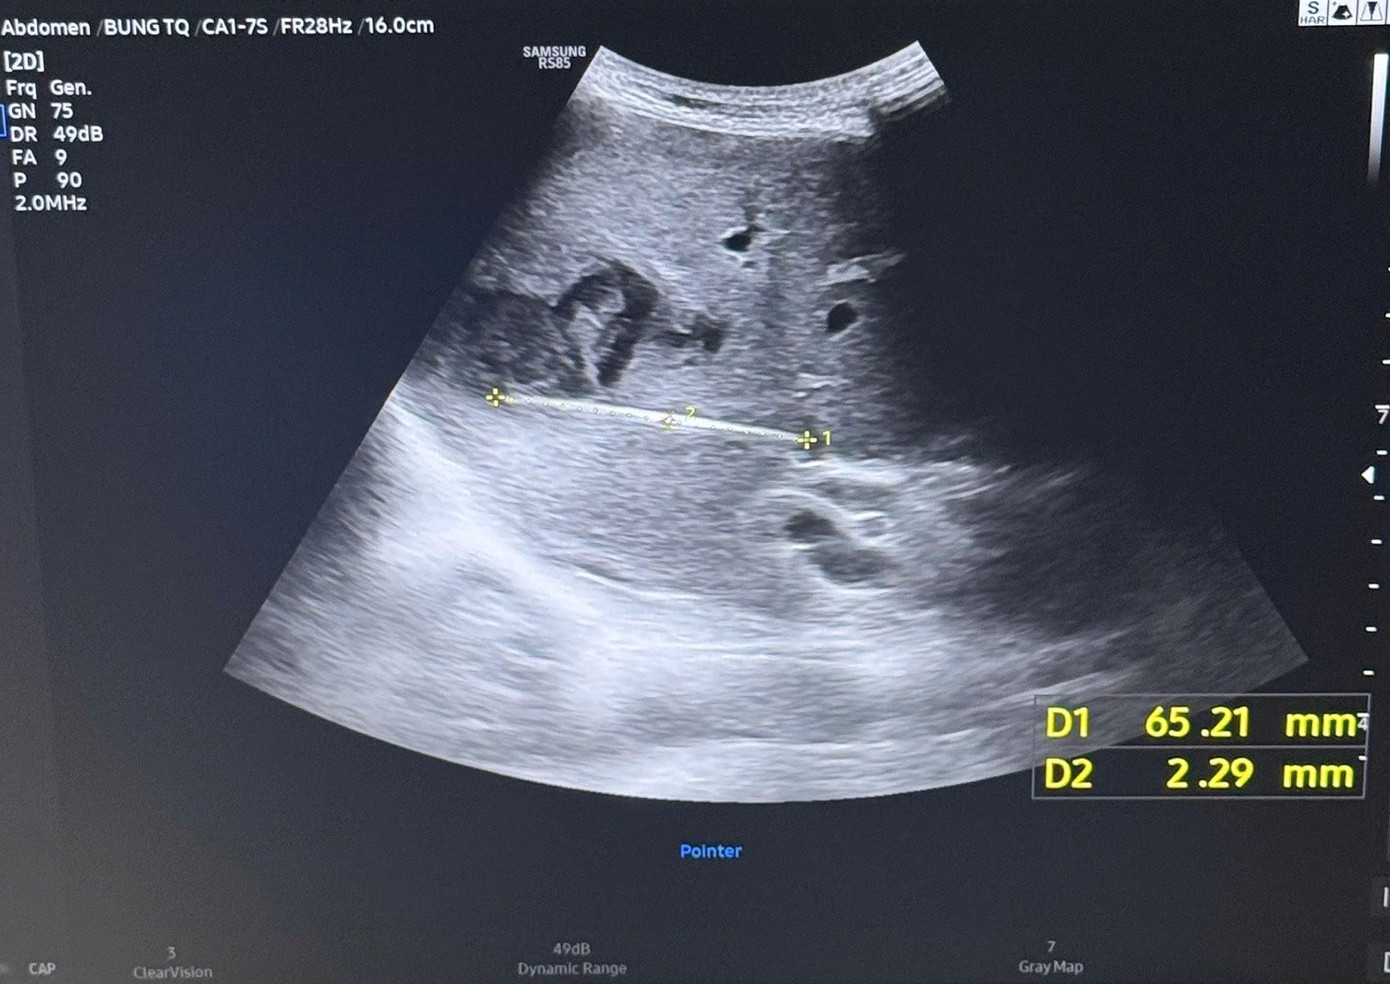

Nguy kịch tính mạng vì thói quen phổ biến sau bữa ăn của người Việt- Ảnh 2.

Sau phẫu thuật, sức khỏe của bệnh nhân đang bình phục tốt

Sau phẫu thuật và điều trị kháng sinh phù hợp, đến nay bệnh nhân đã hồi phục tốt, các dấu hiệu nhiễm trùng cải thiện rõ rệt, dự kiến xuất viện sau khoảng 6 ngày điều trị hậu phẫu.